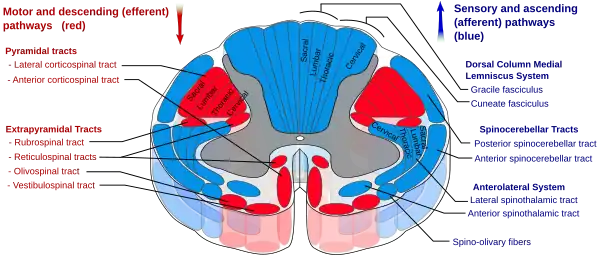

The spinothalamic tract is a sensory pathway originating in the spinal cord. It transmits information to the thalamus about pain, temperature, itch and crude touch. There are two main parts: the lateral spinothalamic tract, which transmits pain and temperature, and the anterior (or ventral) spinothalamic tract, which transmits crude touch and pressure.

Diagram showing the anterior and lateral spinothalamic tracts within the spinal cord